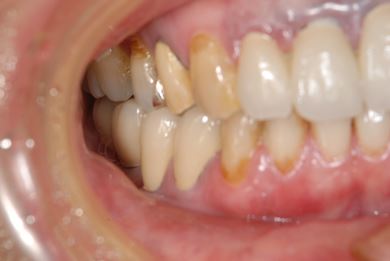

インプラント治療+セラミック治療

| 主訴 | 前歯の黄ばみが気になる。 | ||||||||||||||||||||||||||||||||

| 治療内容 | インプラント3本、ジルコニアフレームオールセラミッククラウン7本(ジルコニア用土台1本)、メタルボンドセラミッククラウン3本(メタルボンド用土台3本)、ハイブリッドセラミッククラウン3本、ハイブリッドセラミックインレー3本 | ||||||||||||||||||||||||||||||||